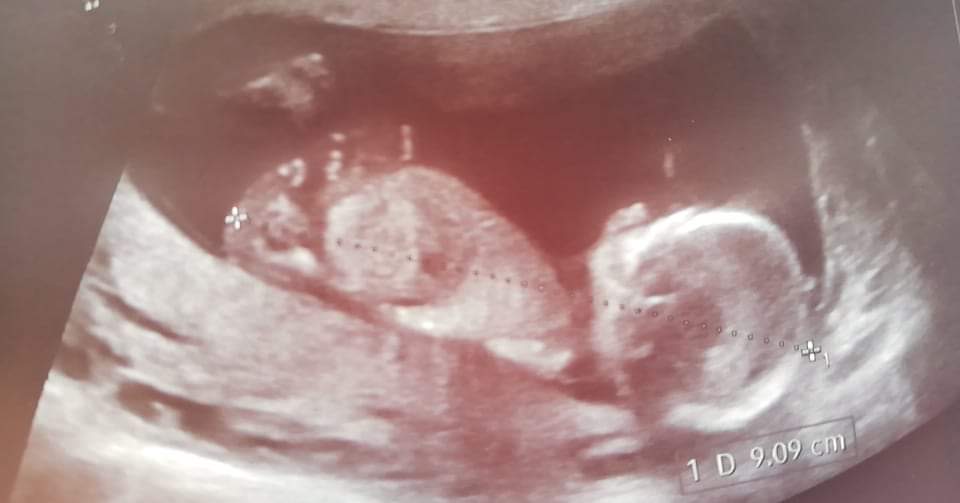

Maleństwo rośnie zdrowo iby tak dalej, l eci 12tc